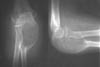

Рис. 7. Стопа. Сенильный остеопороз.